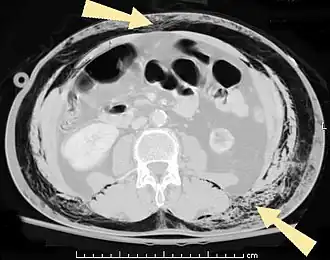

Subcutaan emfyseem of emphysema subcutaneum[1] treedt op als er lucht in het onderhuidse (vet)weefsel aanwezig is. Subcutaan betekent onderhuids, emfyseem opgesloten lucht. Subcutaan emfyseem ontstaat doordat lucht weglekt uit de luchtwegen of een orgaan in de onderhuidse weefsels. Hierdoor treedt pijnloze zwelling op van de huid, die bij aanraking knisperend aanvoelt. Soms wordt dit omschreven als het aanraken van een zakje met gepofte rijst. Met een stethoscoop is dit vaak knetterend te horen.

Subcutaan emfyseem ontstaat vaak als gevolg van letsels van de hals, borstkas of buikholte. Zo wordt het gezien na een fractuur van het strottenhoofd, bij ribfracturen, bij een pneumomediastinum of een pneumothorax, na het inbrengen van een thoraxdrain, na een hart- of longoperatie en soms bij perforaties in de maag of darm.